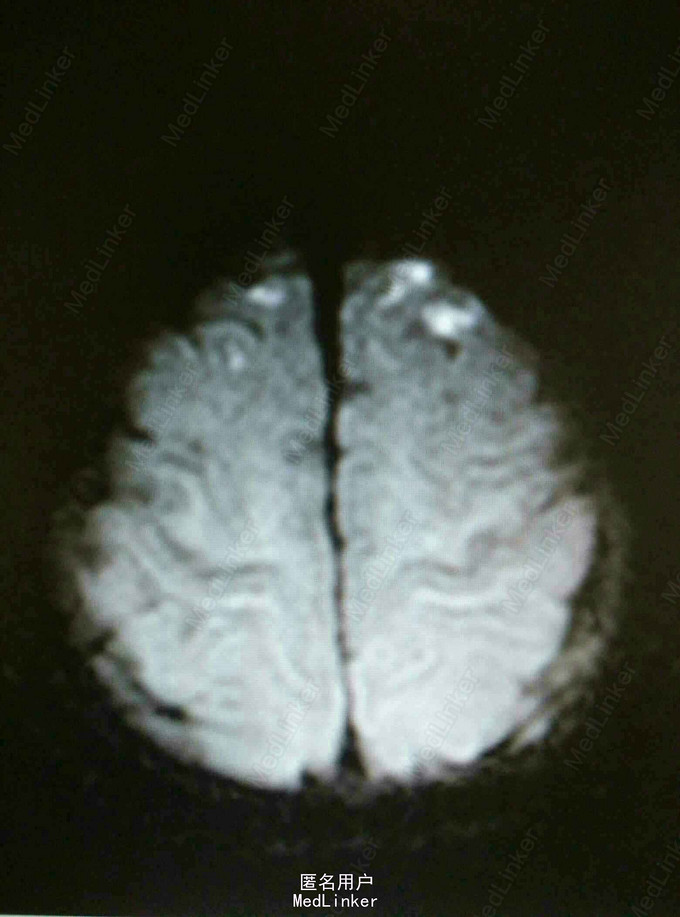

神经系统查体正常。 辅助检查:脑CT:未见明显异常。 进一步头增强MRI如图:FLAIR可见双额叶及顶叶沿皮质走行条状高信号,DWI可见双额叶点状明显高信号及顶叶脑回略高信号,增强脑实质未见异常,上矢状窦空三角征不很明确,T1无明显异常。

进一步MRV检查提示上矢状窦远端血栓形成。 诊断为上矢状窦血栓形成。 治疗予以低分子肝素抗凝及甘露醇脱水,好转出院。